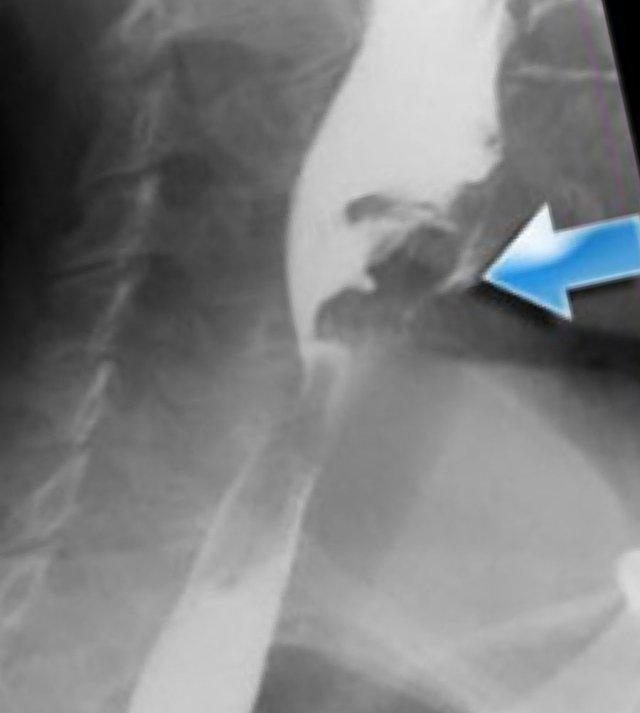

Rối loạn chức năng cơ nhẫn hầu

Mở không đủ và đóng sớm là những vấn đề thường gặp nhất của cơ nhẫn hầu.

Bình thường không nên thấy vết lõm của cơ nhẫn hầu trong quá trình bolus đi qua, nhưng đôi khi thấy một vết lõm nhỏ không gây tắc nghẽn và không có ý nghĩa lâm sàng (Hình).

Tuy nhiên, đôi khi điều này có thể giải thích các triệu chứng của bệnh nhân.

Người ta cho rằng sự đi qua của thức ăn kích thích niêm mạc phủ trên cơ nhẫn hầu, gây ra cảm giác vướng họng (globus sensation).

TRÁI: túi thừa nhỏ. GIỮA và PHẢI: túi thừa Zenker thực sự do đóng sớm của cơ nhẫn hầu (mũi tên vàng)

Túi thừa Zenker

Túi thừa Zenker luôn là hậu quả của rối loạn chức năng cơ nhẫn hầu.

Đóng sớm của cơ nhẫn hầu dẫn đến tăng áp lực trong hạ hầu, ngay phía trên cơ nhẫn hầu, khi sóng áp lực của các cơ khít hầu đẩy bolus xuống dưới.

Áp lực tăng này có thể gây phồng ra tại điểm yếu trên thành hầu sau (khe hở Killian).

Ban đầu sẽ tạo thành một túi nhỏ, theo thời gian có thể phát triển và hình thành túi thừa Zenker thực sự (Hình).